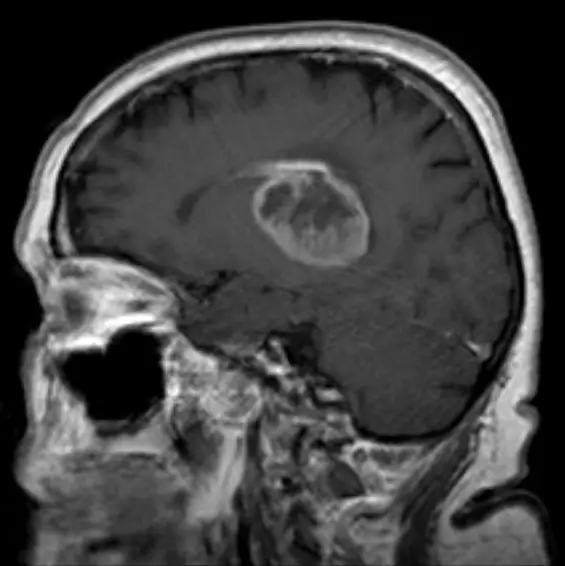

Хирурги сосредоточились на лечении злокачественной глиомы, самой опасной и распространенной формы опухоли головного мозга. Средний пациент с таким заболеванием живет всего 15 месяцев после постановки диагноза. Однако после встречи с двумя пациентами с глиобластомой, которые жили 15 и 20 лет после постановки диагноза их состояния, Муйзелаар увлекся идеей разработки лечения смертельной болезни.

Начиная с 2010 года врачи провели процедуру у трех пациентов со злокачественными опухолями головного мозга, поместив бактерии в их открытые раны на голове. Процедура не увенчалась успехом. К публикации этой статьи все пациенты умерли. Двое умерли вскоре после этого от сепсиса; у пациента, который прожил дольше всех, действительно уменьшилась опухоль головного мозга, но была раневая инфекция. Через десять месяцев после процедуры этот пациент был вынужден принимать антибиотики и с тех пор умер.